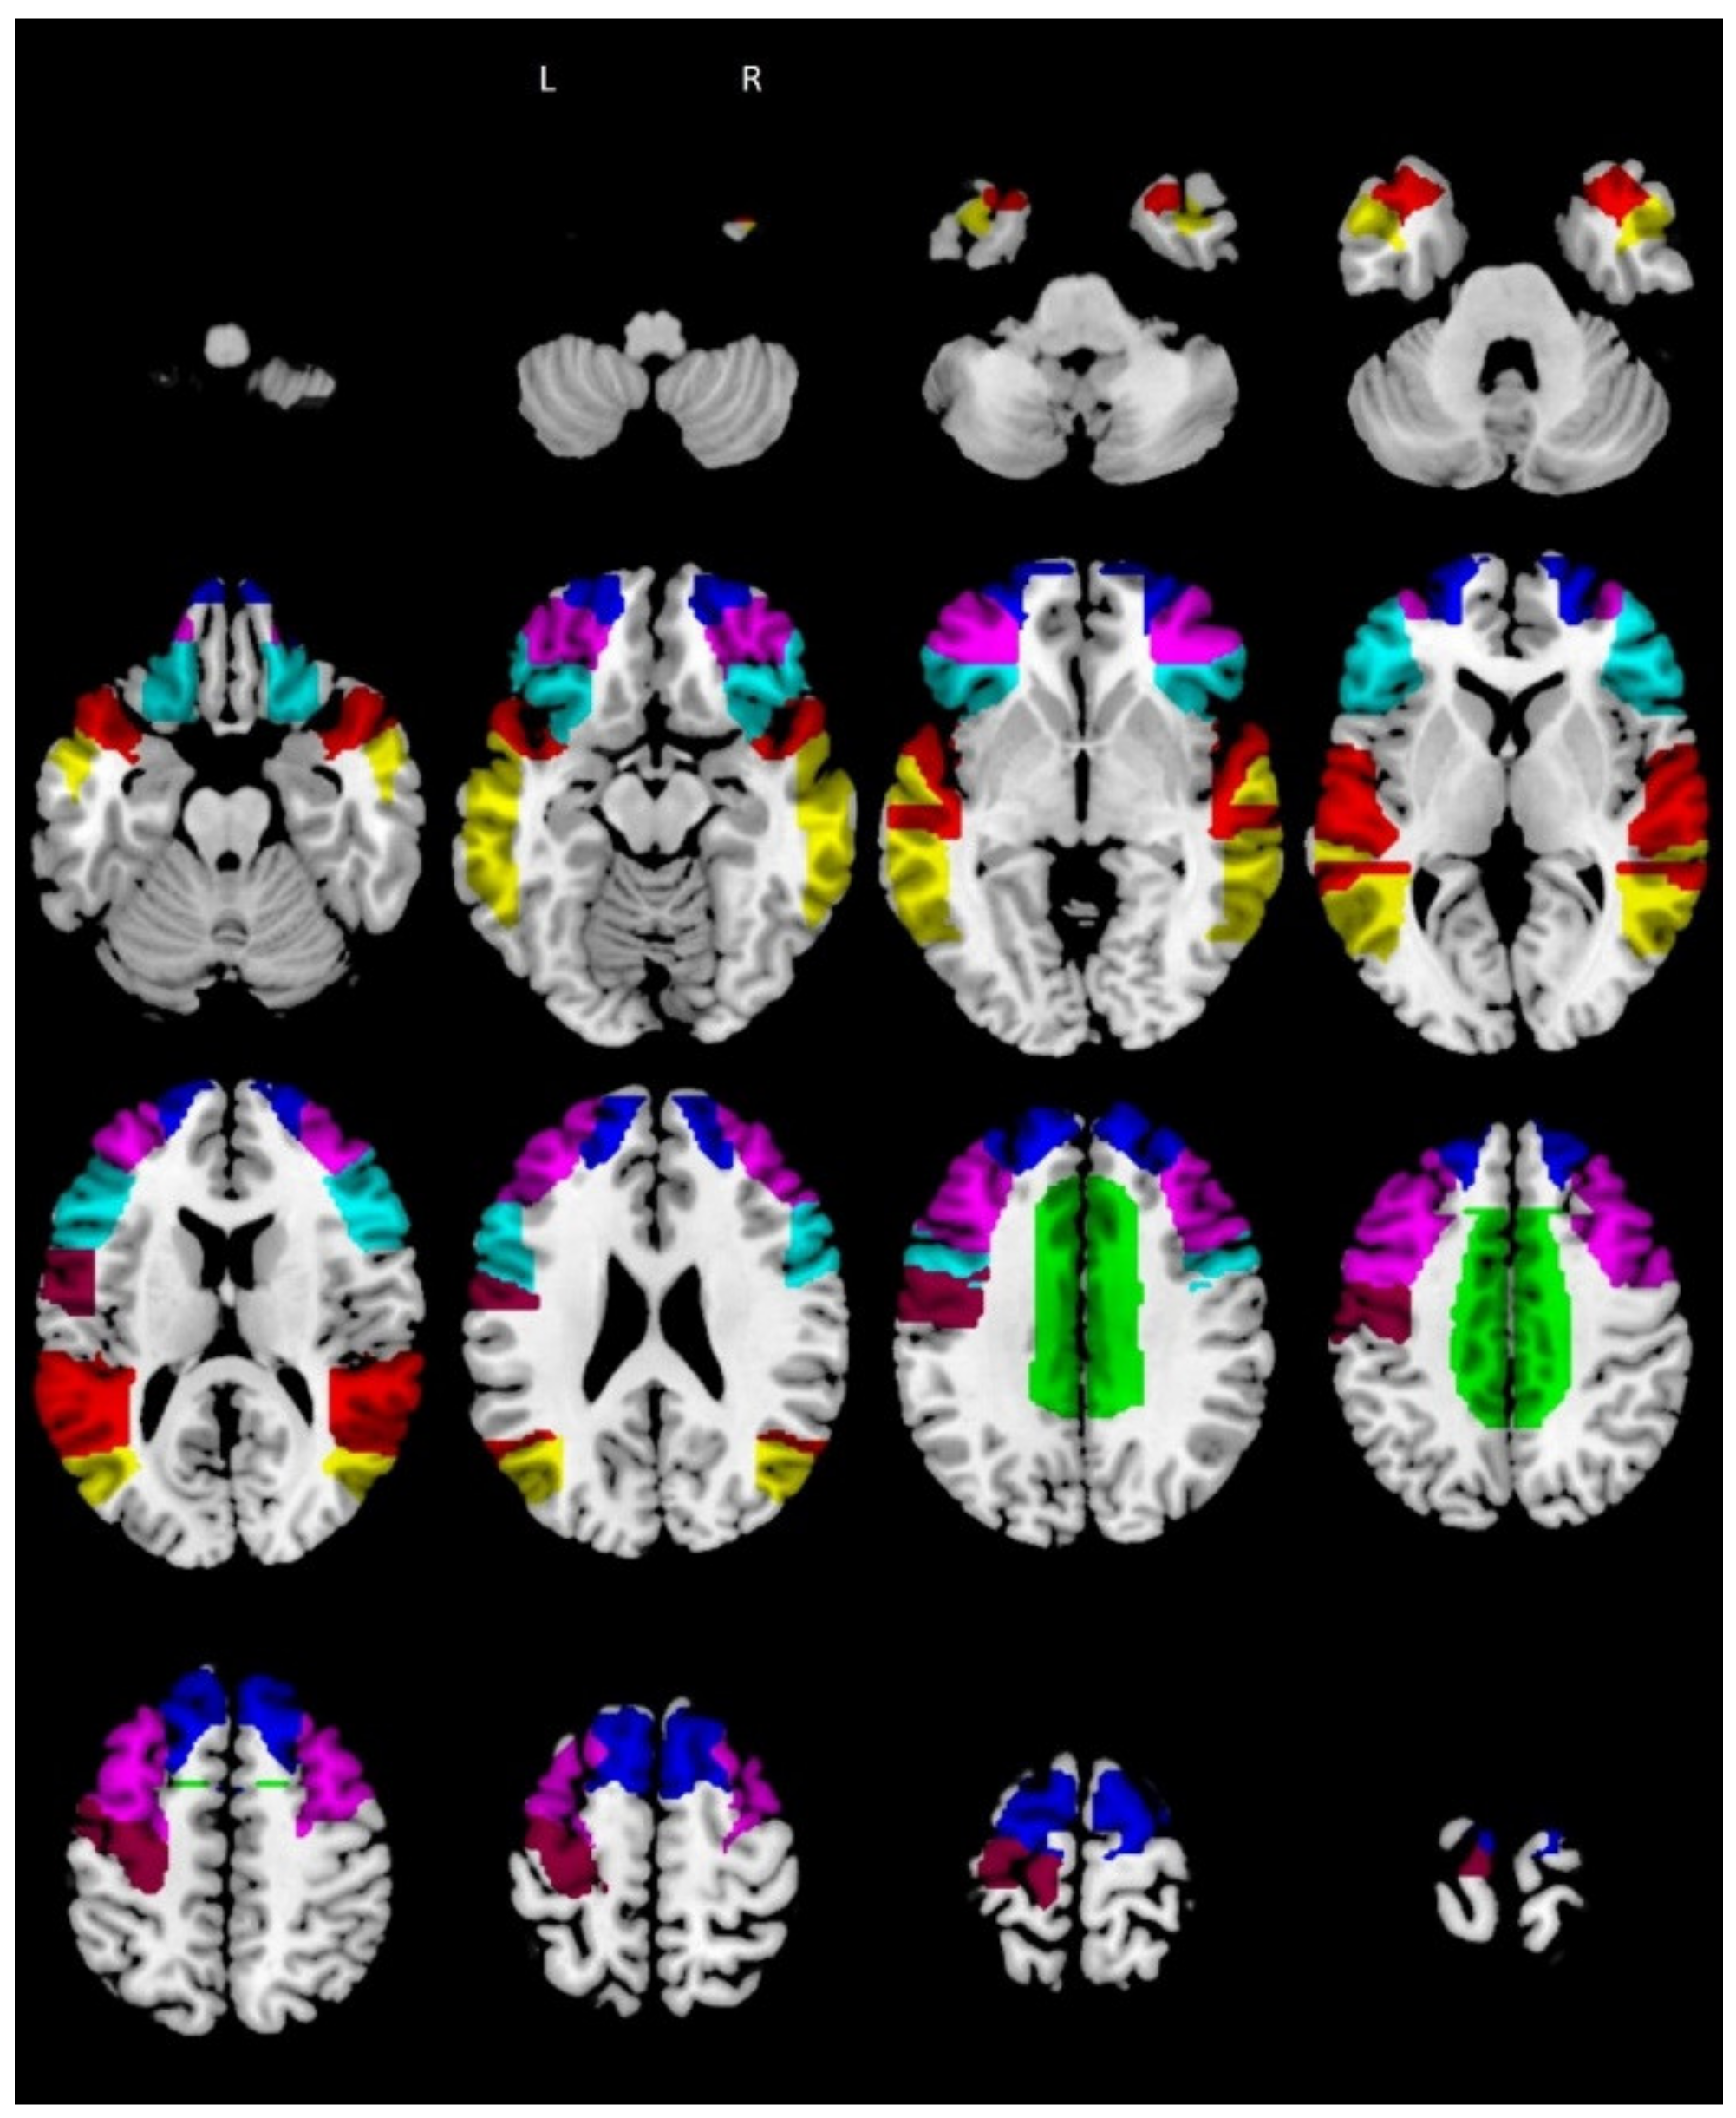

We created these ROIs using the WFU PickAtlas toolbox for SPM12 (Figure 1).

Figure 1.

RMET ROIs according to Molenberghs et al. (2016) (RMET = Reading the Mind in the Eyes task; R = right; L = left; ROIs = regions of interest). Legend: green = R/L cingulate gyrus; cyan = R/L inferior frontal gyrus; blue = R/L superior frontal gyrus; violet = R/L middle frontal gyrus; yellow = R/L middle temporal gyrus; purple = left precentral gyrus; red = R/L superior temporal gyrus.